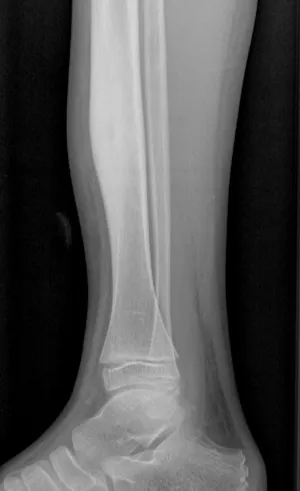

Osteomyelitis with Codman's triangle

XRAYHandInfection+2